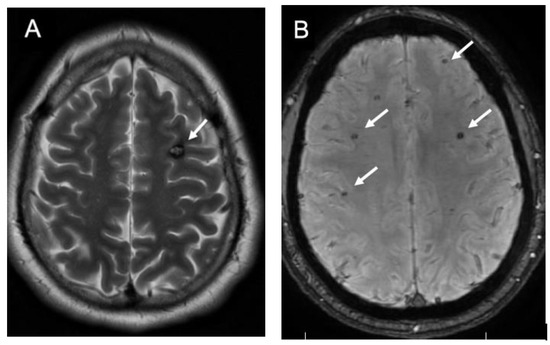

2. Epidemiology and Genetics of CCMs

3. Diagnosis